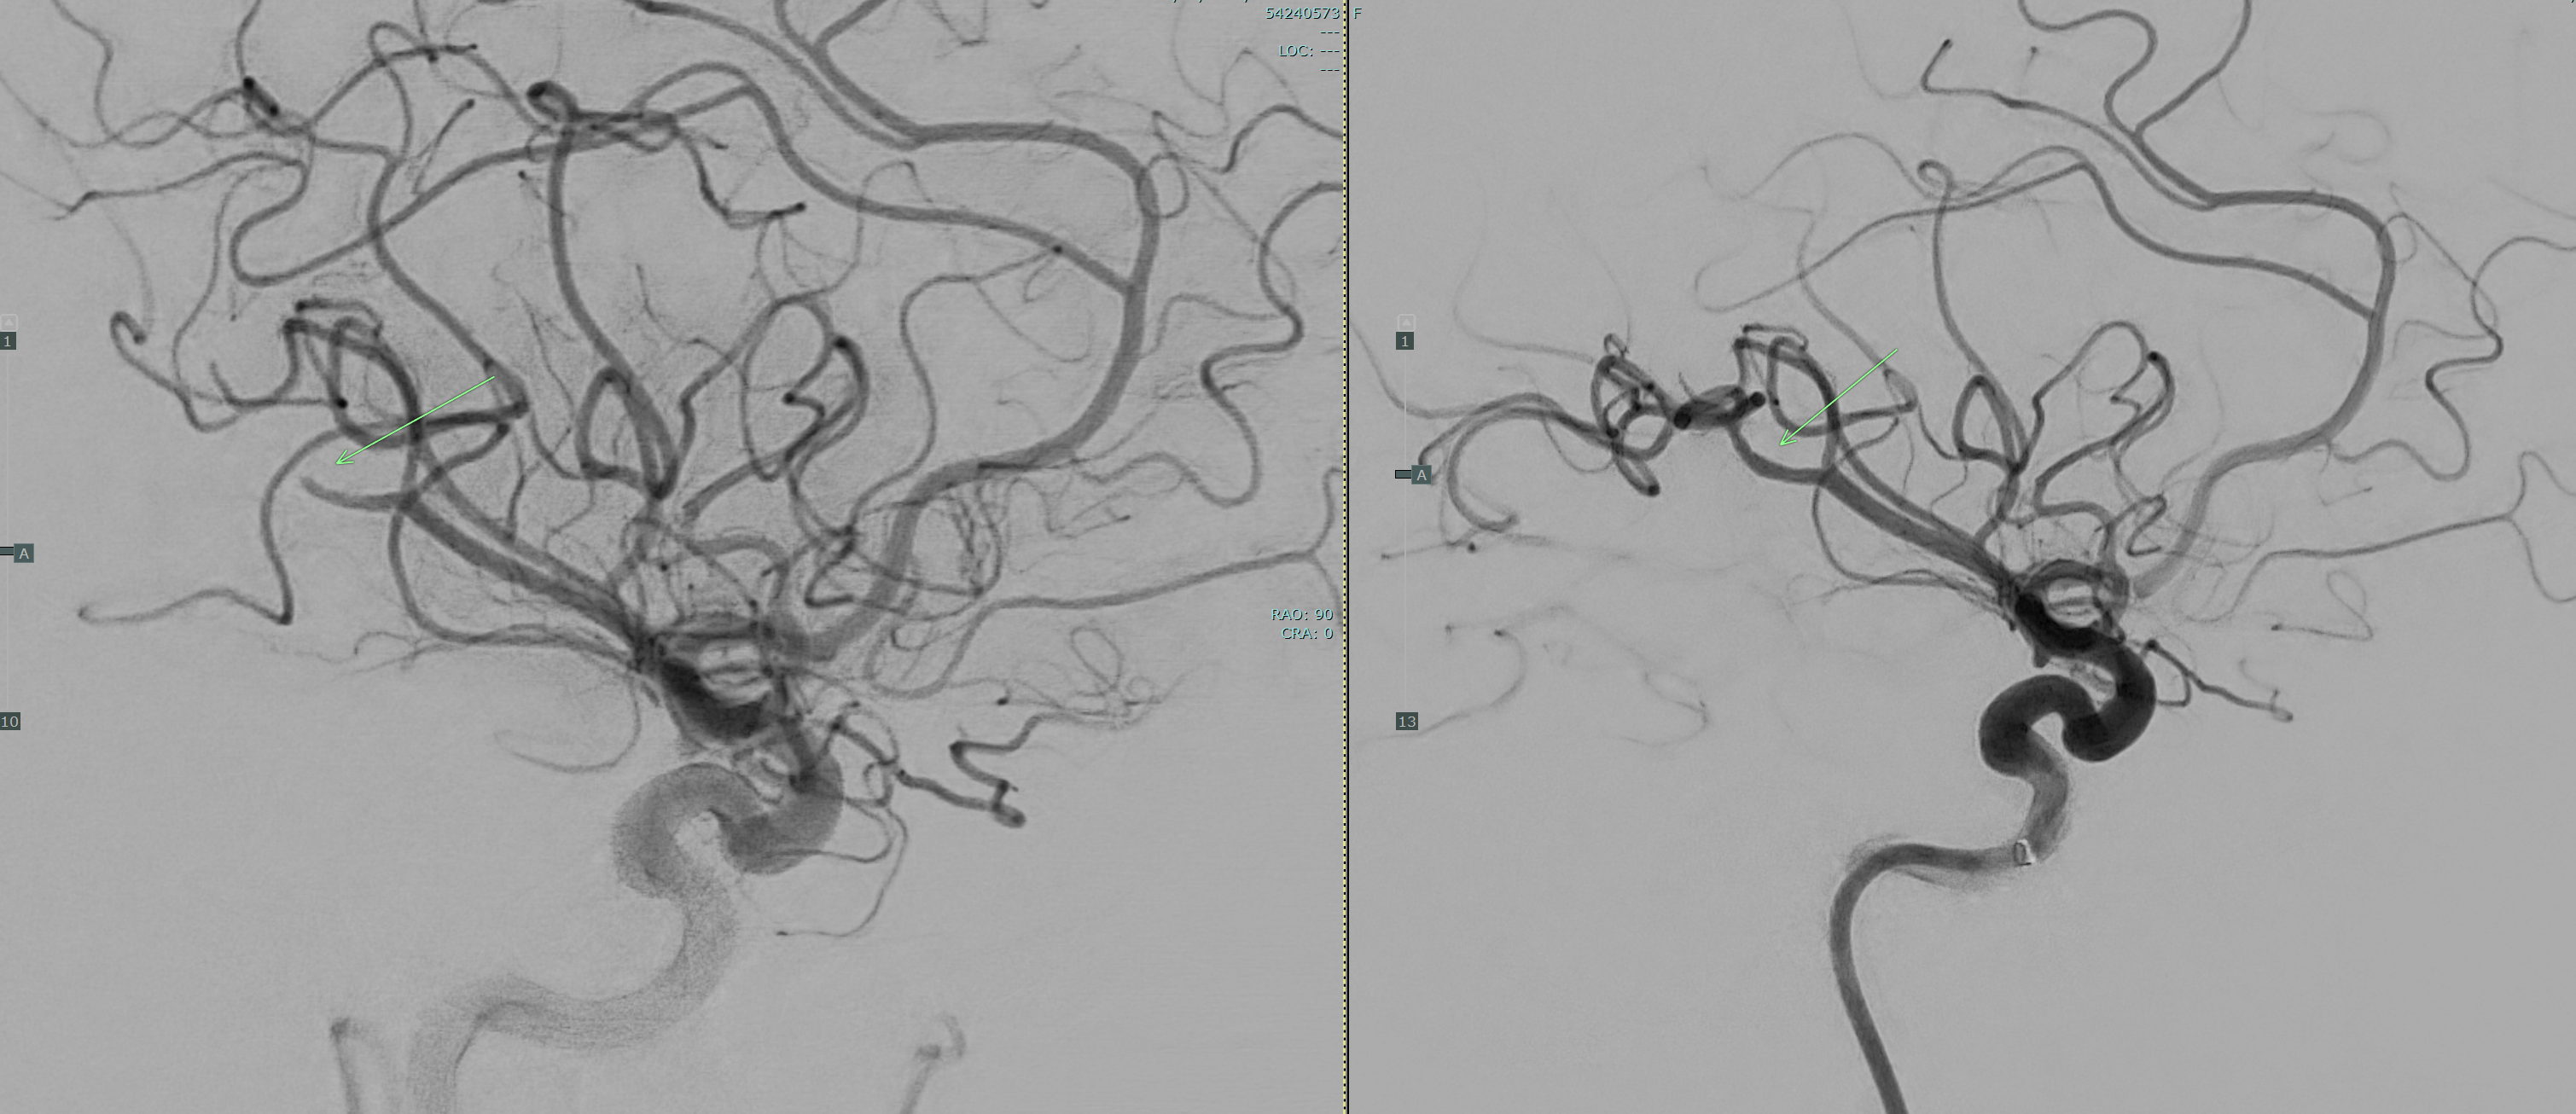

Neurosurgeon Dr. Jeyan Kumar removed the blood clot from her brain by performing a thrombectomy, which involves using a small catheter to clear the vessel. After the procedure, Butcher stayed in the intensive care unit for a few days before going home with no paralysis or speech issues.

Angio images